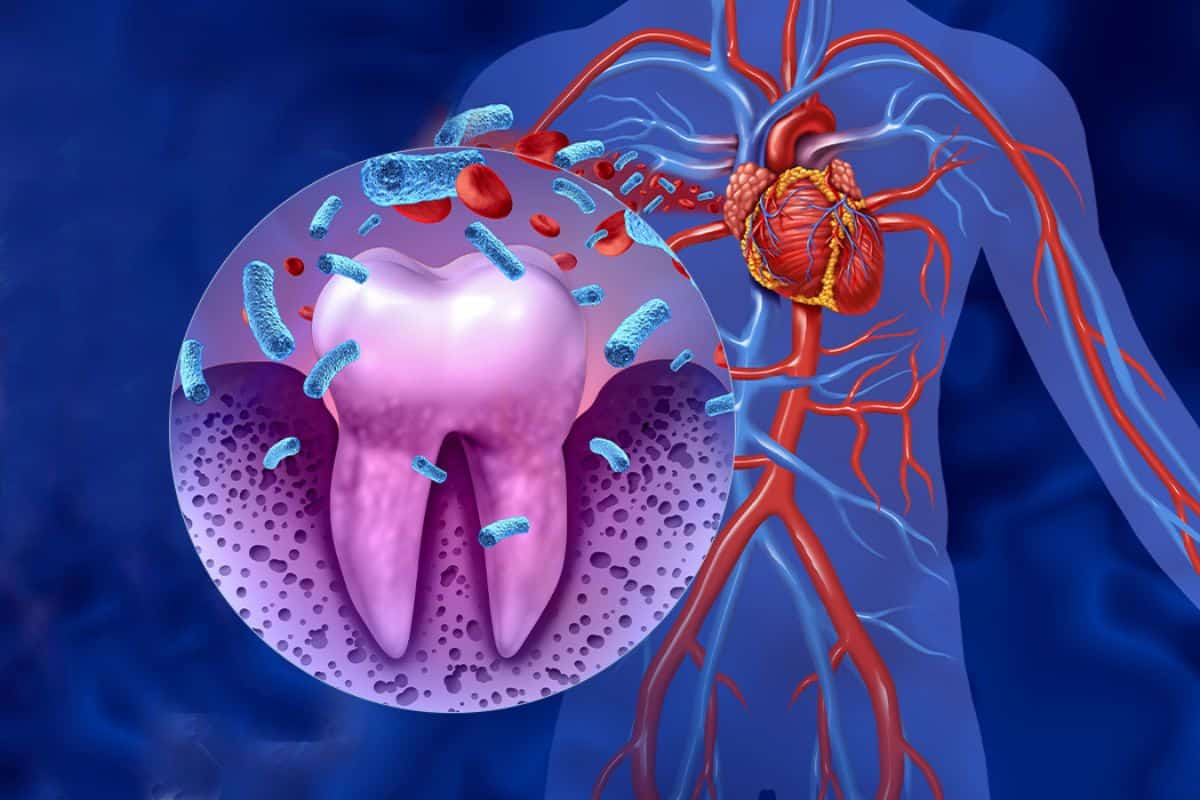

O corpo todo paga

A periodontite é uma infecção crônica: as bactérias entram na corrente sanguínea pela gengiva inflamada. Isso tem efeitos no corpo todo, comprovados pela ciência:

"Não há saúde sem saúde bucal. E não há saúde bucal sem saúde gengival." — OMS